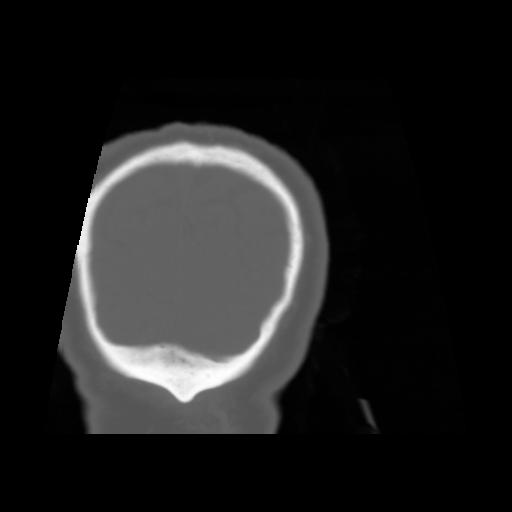

5 CEREBRO,,Coronal,3.000,CEREBRO,Coronal,